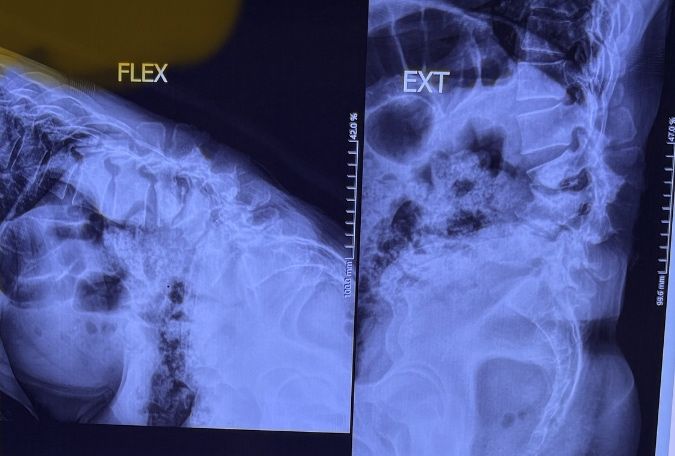

Since I’ve noticed instability in some segments I asked for dynamic L/S x ray:we see mild L4 ant listens due to DjD/DDD. There is not any pars defect.